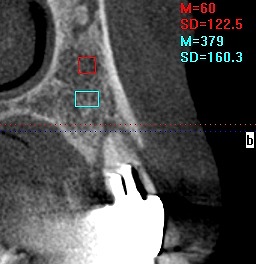

深埋めなので骨と当たっています 確認用のデンタルレントゲン

4番のインプラントになります

5番の傾斜埋入にインプラントになります